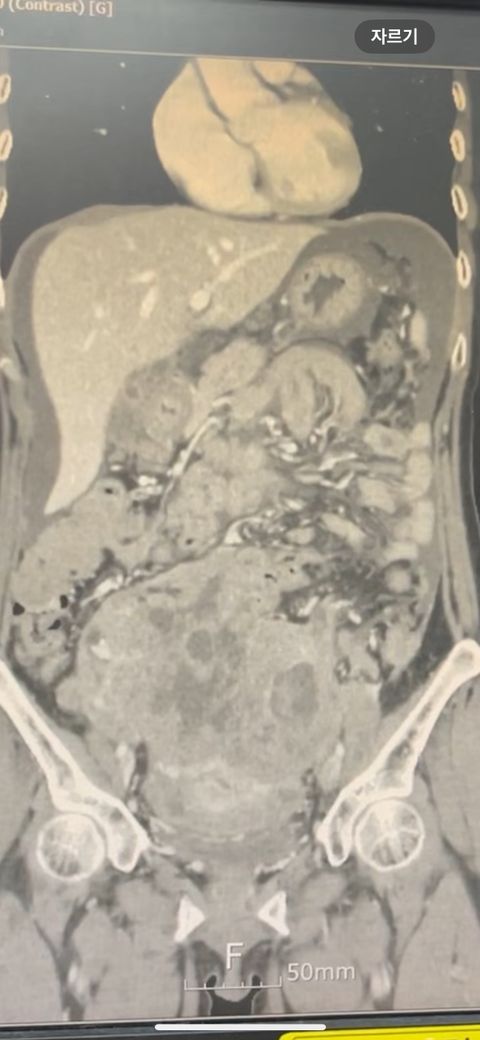

복부 ct 판독 부탁드립니다 (contrast)

결과는 3일 뒤 보긴 하는데 우선 영상만 있는 상태라 영상 캡쳐 한 거 대략적으로라도 확인해주실 수 있나요.. !!!!!!!!!!

• 1번 째 사진

*** 먼저 답변드리기에 앞서 상기 질문에 대한 답변은 굉장히 제한된 답변이고, 경우에 따라 틀린 답변이 될 수 있습니다. CT의 경우 단면을 연속적으로 봐야 의학적인 설명이 가능하기 때문에 일부 사진만으로는 해석이 어려울 수 있습니다.

위 사진에서는 비장비대의 가능성과 자궁쪽으로 혹이 일부 보이는 소견이 의심되나, 정확한 판독은 3일 뒤에 받아보시는 것이 도움이 될 수 있겠습니다.